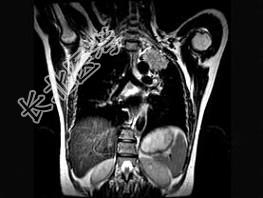

- 单项选择题男,68岁, 声音嘶哑半月,行MRI检查如图, 其最可能的诊断为 ( )

A、右上肺癌

B、左上肺结核球

C、左上肺炎性假瘤

D、左上肺癌

E、左上肺动静脉瘤